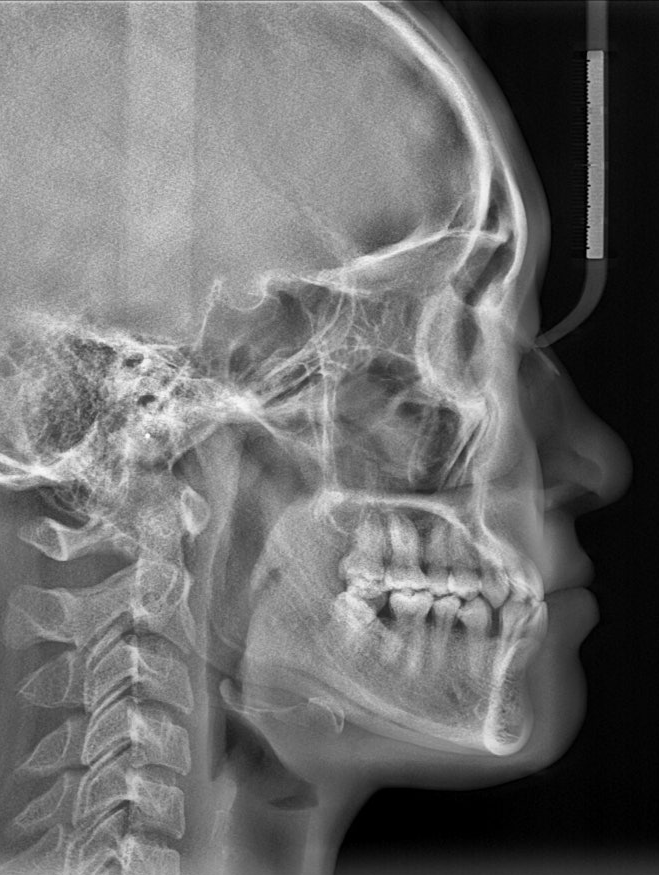

¹æ»ç¼± »çÁø»ó¿¡¼

¾Æ·¡ÅÎÀÌ À§Åο¡ ºñÇØ Àü¹æÀ¸·Î µ¹ÃâµÈ °ÍÀ» È®ÀÎÇÏ¿´½À´Ï´Ù.

¹æ»ç¼± Ãø¸ð »çÁø¿¡¼µµ

ÁÖ°ÆÅÎ °æÇâÀÌ ÁÙ¾îµç °ÍÀ» È®ÀÎÇÒ ¼ö ÀÖÀ¸¸ç

ÀÔ¼ú¼±ÀÌ °³¼±µÇ¾ú½À´Ï´Ù.